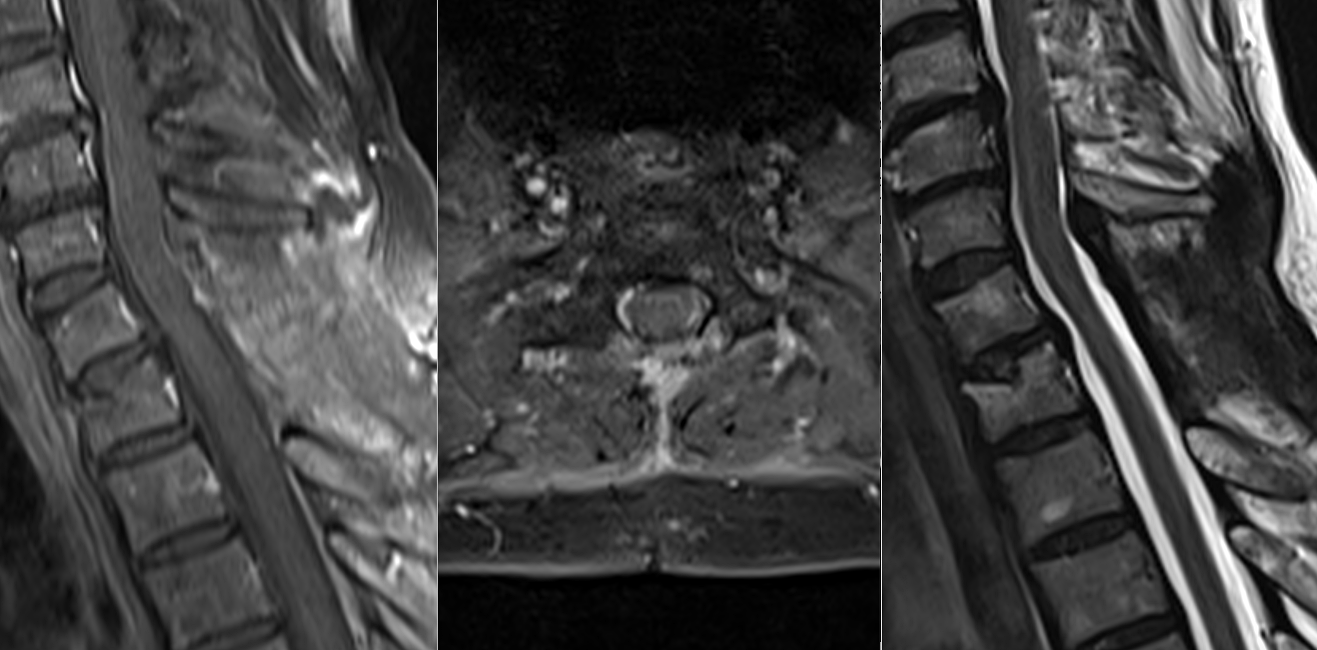

Tumoră intramedulară toracală – ependimom

Meningiom spinal toracal cu compresiune medulară severă